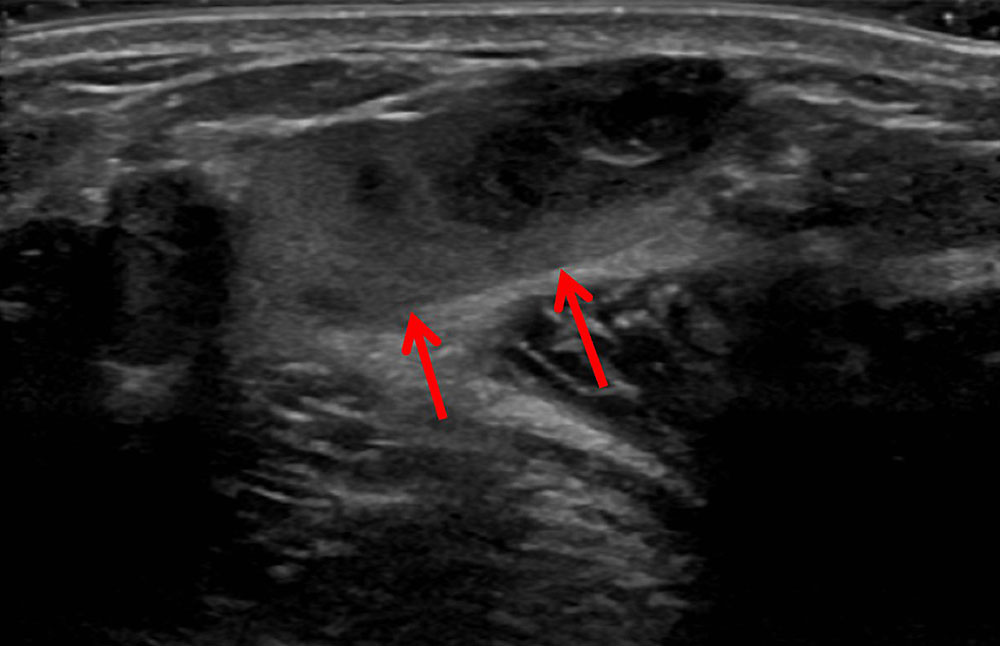

• Extensive thrombi within the venous malformation in imaging (especially visible in MRI and sonography) and large-volume intramuscular venous malformation